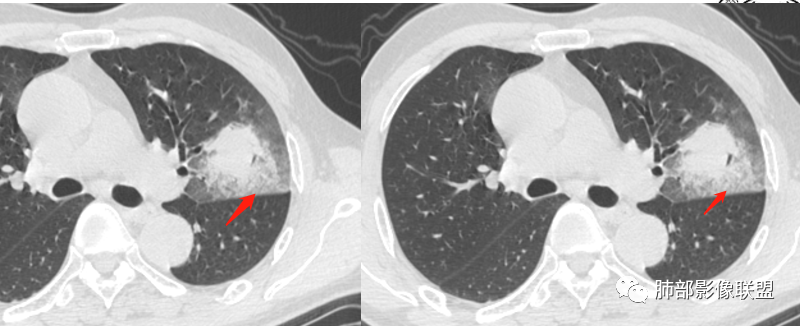

周围磨玻璃影是飘出去的粘液,也是肿瘤的一部分吧?

@小赵 这个不一定是粘液,很可能还是周围癌性浸润。看术前复查,原磨玻璃区呈明显小叶间隔增厚改变了。说明还是癌性淋巴浸润。

癌细胞气腔播散?癌性淋巴道炎?黏液?阻塞性?肺出血?

@温附一影像科,傅钢泽 应该是STA(气腔播散)加癌性淋巴管炎。

支气管稍扩张→有张力,GG0边缘清楚,局部有小叶间隔阻挡。

反思,恶性膨隆,远端空洞,强化坏死不均,里面血管似乎也是增粗,边界不清,似乎有侵犯。坏死还是边界不清。

1、团片状,实行密度区外观整体圆顿,位于上叶尖后段与下舌段区间。局部膨隆,但未见分叶,肿瘤多见。

2、偏心空腔病灶,气腔略呈新月形,壁不规则,腔内结节相对密实,明显强化且不均,支持新生物而非曲菌球等。炎性空洞多有强化环。

3、病变强化较明显,其内隐约显示多发小斑片状无强化灶,可疑边界不清小灶坏死区。病灶内血管影浅淡、模糊不规则。

4、支气管改变:上舌段支气管远段延入部分稍示僵硬。尖后段见分支支气管阻塞,恶性多见。

5、周围磨玻璃,3个月后逐渐转为密实,应符合当初附壁生长为主,且逐渐向实体成分转换。

6、病变长轴平行且受限于胸膜,外围大内带小,符合外朝内发展病变。“腔内结节状明显强化”加之支气管改变有力支持新生物诊断。如此大范围边界不清的磨玻璃影让人浮想联翩。如此大范围病灶,肺门纵隔未见肿大淋巴结也让人意外。